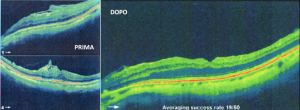

Sei in: Home / VITRECTOMIA MINI-INVASIVA PER IL TRATTAMENTO DELLA PUCKER MACULARE: / Schermata 2015-12-10 alle 19.58.26